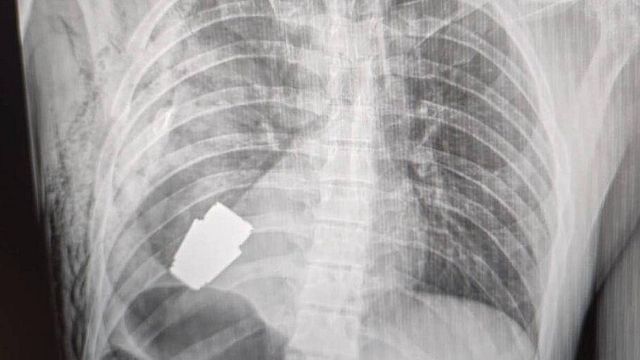

La vice ministra ha pubblicato l'immagine di una radiografia in cui si vede l'ordigno all'interno del corpo del soldato e una foto del chirurgo che tiene in mano l'esplosivo dopo l'intervento. "I medici militari hanno effettuato un'operazione per rimuovere una granata Vog, che non è esplosa, dal corpo del soldato", ha scritto Maliar nel post su Facebook.

In Ucraina, durante un intervento chirurgico, una granata inesplosa è stata rimossa dal torace di un soldato. Lo ha reso noto su Facebook la vice ministra della Difesa ucraina, Hanna Maliar. "La granata poteva esplodere in qualsiasi momento", ha sottolineato Maliar aggiungendo che due artificieri erano presenti durante l'intervento per assicurarsi che fosse condotto in sicurezza. Il chirurgo ha estratto l'ordigno da appena sotto il cuore del militare ferito.

"La parte inesplosa della granata è stata prelevata da sotto il cuore. La granata non è saltata in aria, ma è rimasta esplosiva", ha scritto su Telegram il consigliere ministeriale per gli affari interni dell'Ucraina, Anton Gerashchenko, definendo l'intervento come uno di quelli che "entreranno nei libri di testo di medicina". Una squadra di artificieri ha in seguito neutralizzato l'ordigno, ha aggiunto Gerashchenko.